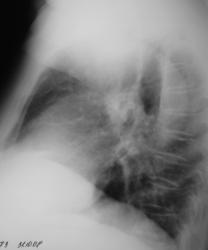

Иллюстрации 4 и 5. Рентгенограмма, и её фрагмент с увеличением в правой боковой проекции.